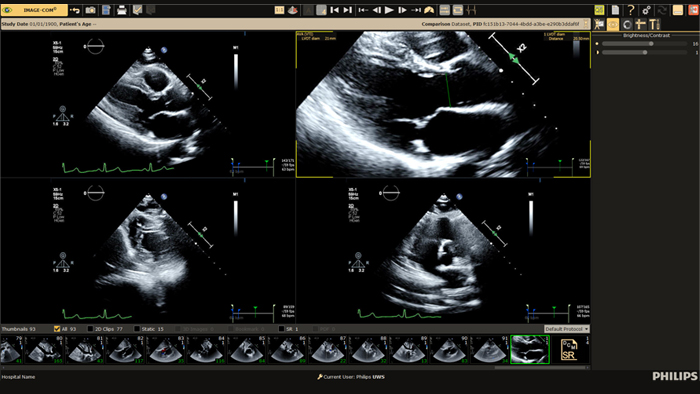

Ultrasound Workspace

Allow for greater efficiency in viewing, analysis and reporting by giving care teams the flexibility to adopt different workflows based on their current and future needs.

Cardiac Ultrasound

Enhance diagnosis confidence and clinical efficiency through superior image quality, advanced quantification tool and automation technology.